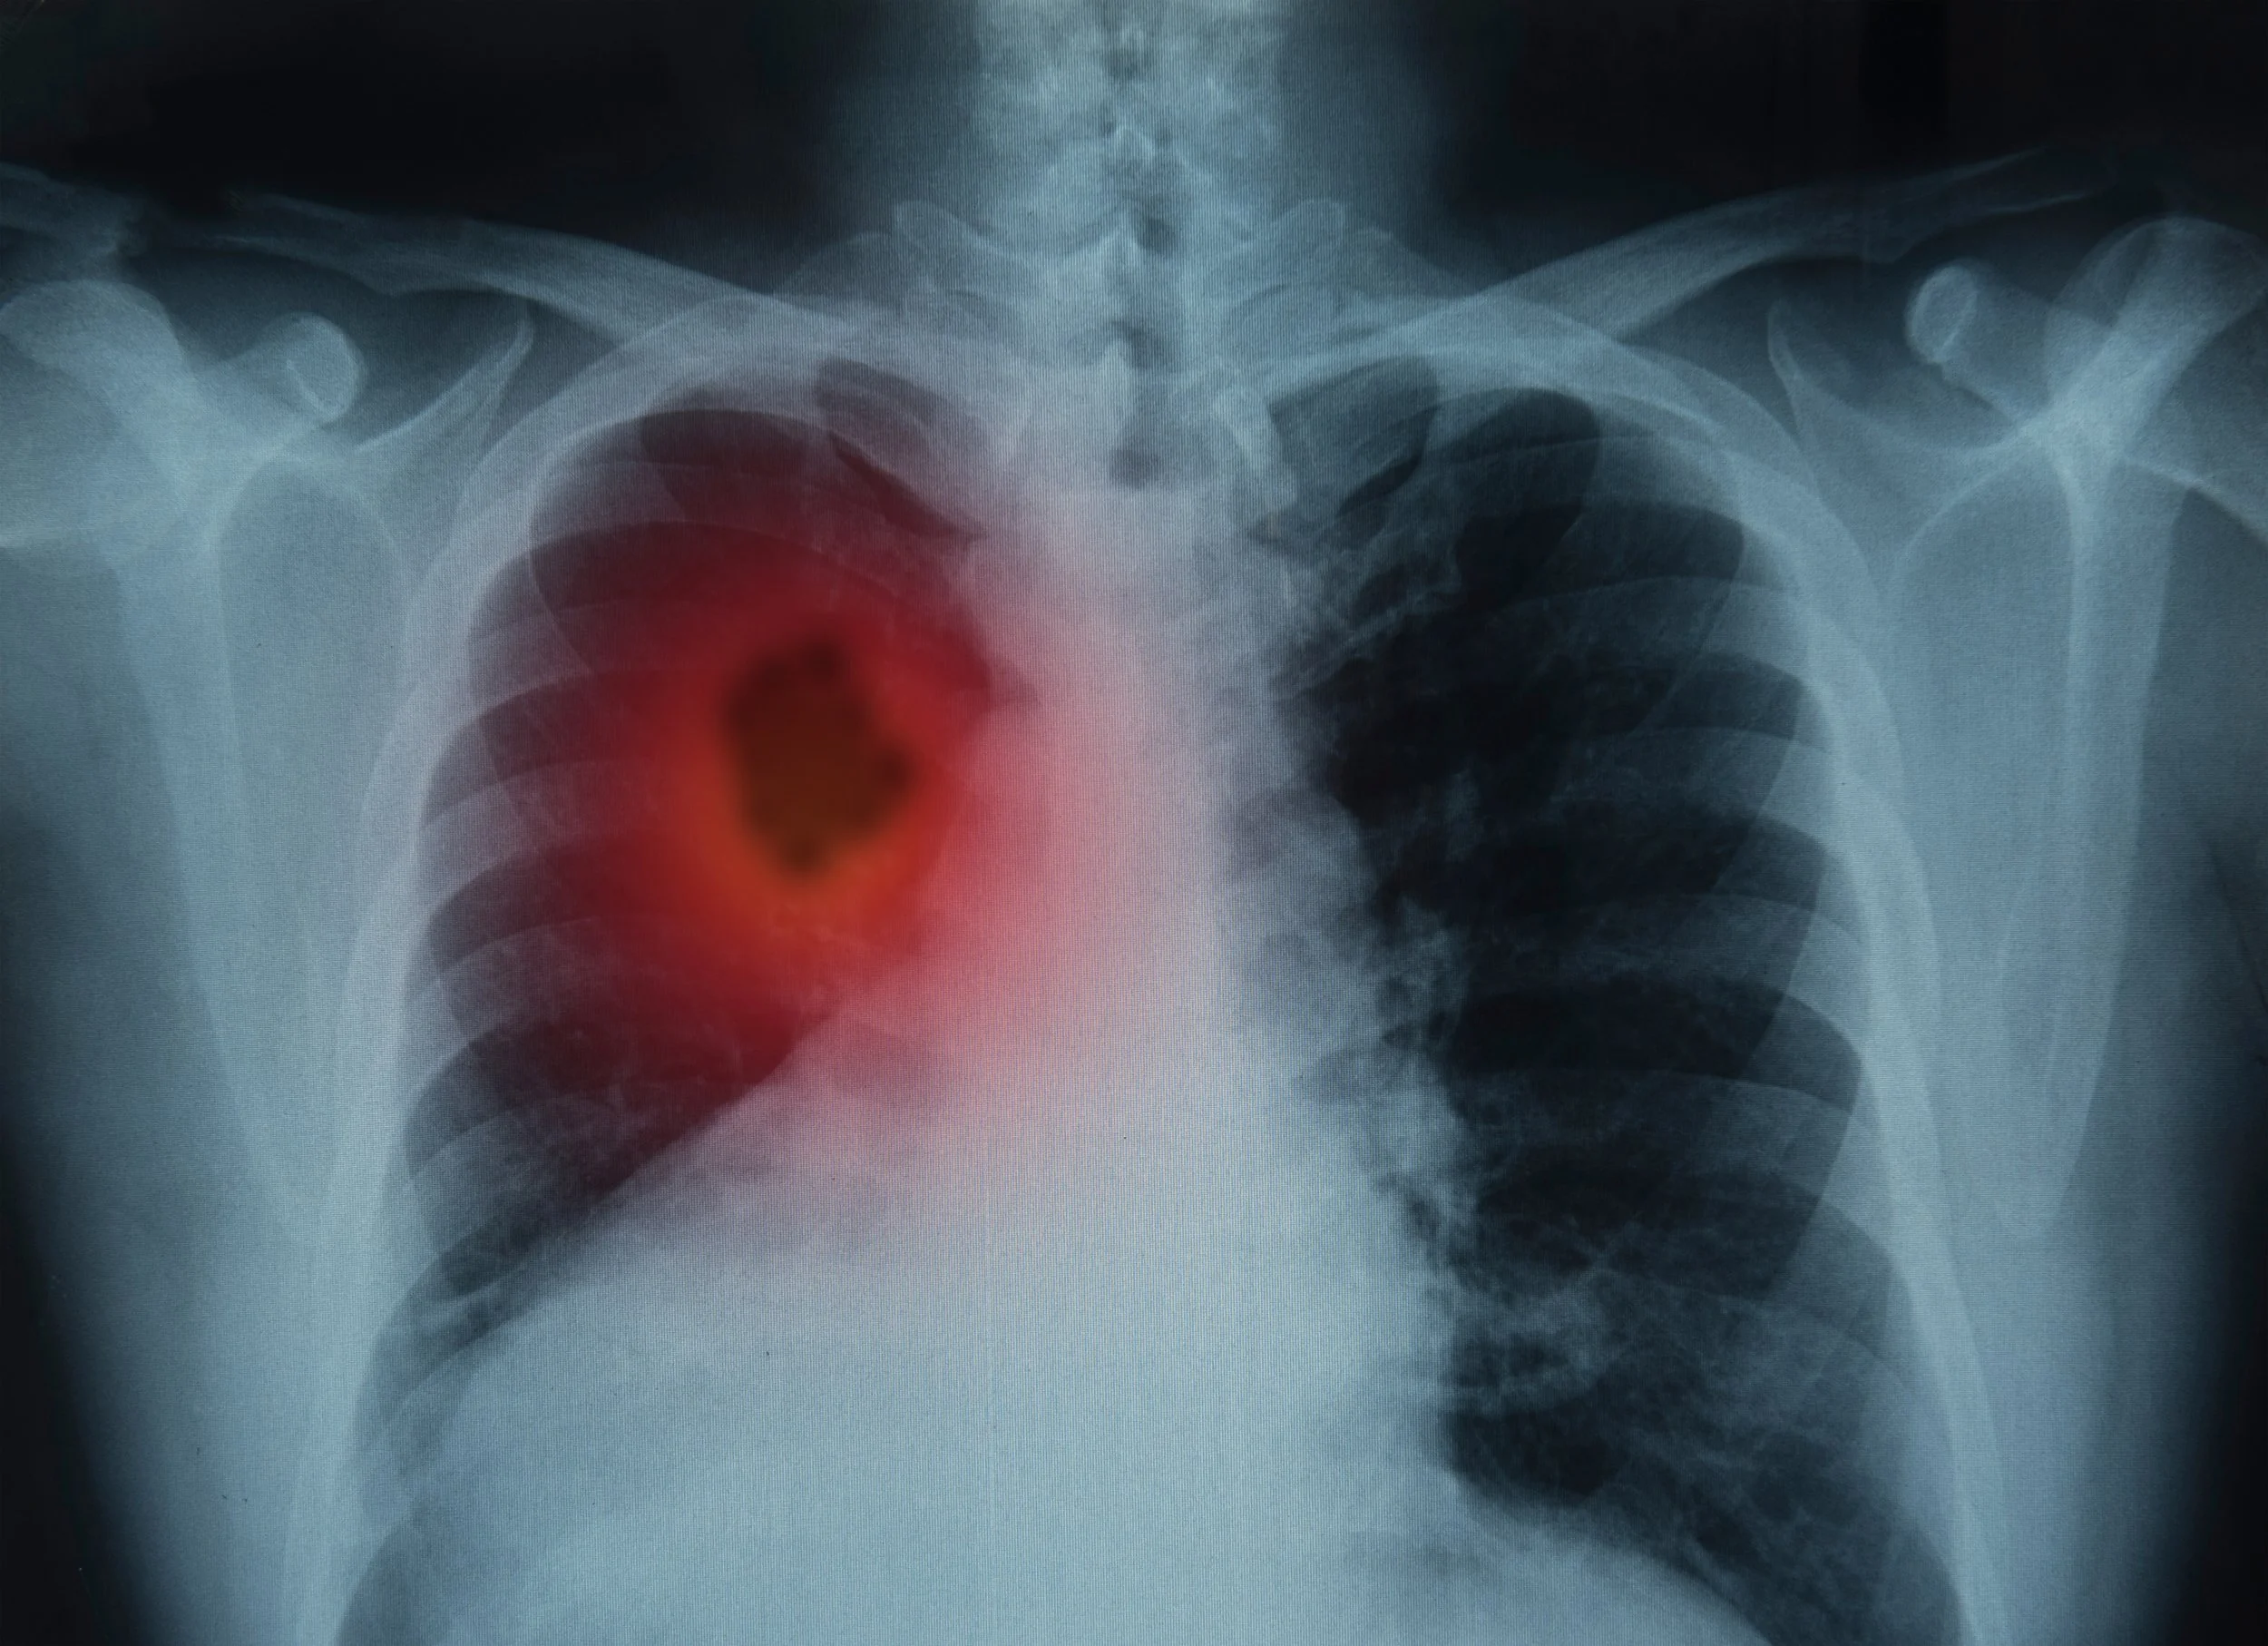

medical scan of lungs

Lung cancer is a very serious—and sometimes, scary—topic. Lung cancer is the second most common cancer in both males and females. Each year, about 228,150 new cases of lung cancer are diagnosed. Both treatments and prognoses for lung cancer vary depending on the type and stage of cancer. Lung cancer can be difficult to diagnose in its early stages, but catching it early can significantly improve patient outcomes. That’s why it’s so important for people to recognize the symptoms and know what to watch for. Visiting a trusted lung care specialist can make all the difference. Our team of dedicated experts is committed to guiding you through every step of the diagnostic process, including enrollment in our comprehensive Lung Cancer Nodule Program.